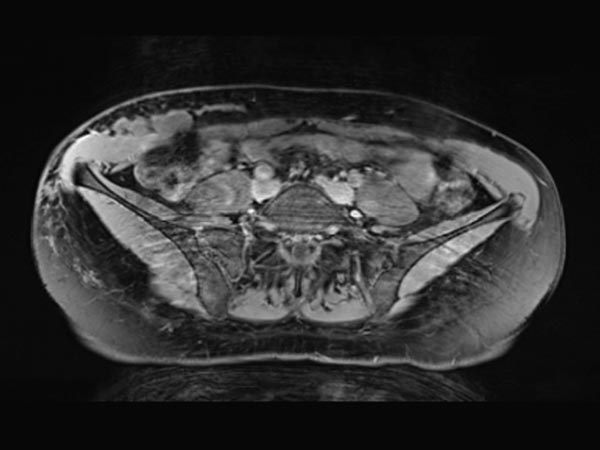

Gleiche Schnittführung in der nativen T1-Wichtung (MRT). Die Zysten der lymphatischen Malformation sind isointens zur Muskulatur. Damit keine lokale Einblutung.